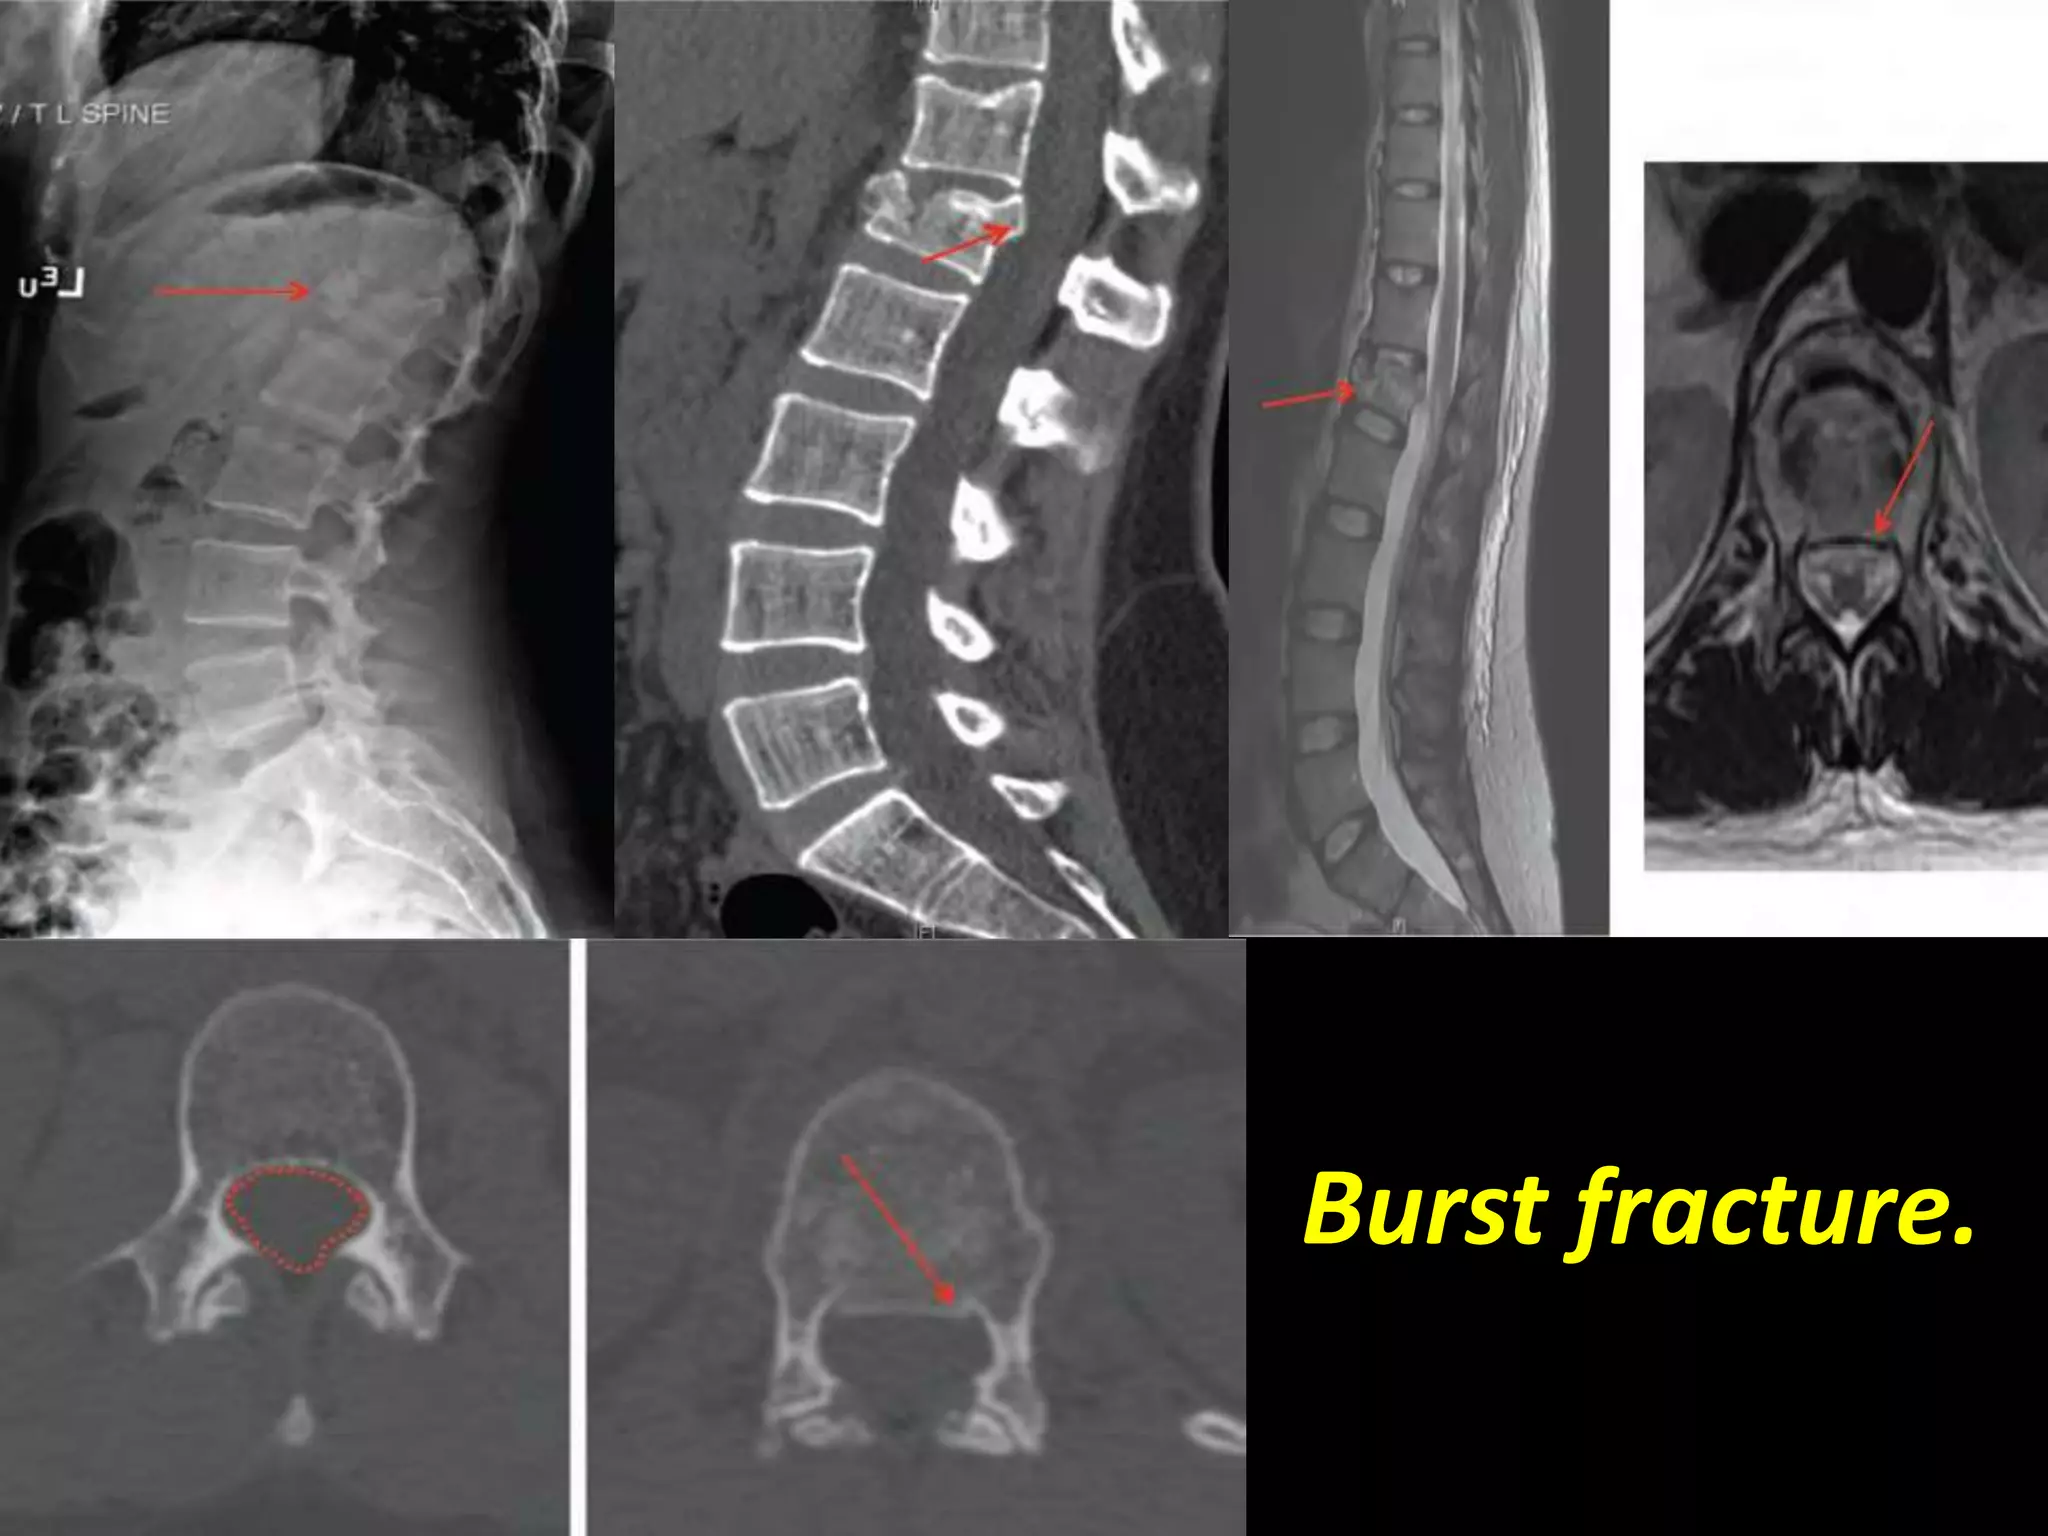

Coronal T2W image dorso lumbar spine of a 29 yr old male

patient showing burst fracture(arrow) of L3 vertebra.

Burst fracture.

Burst vs. Anterior Wedge Fx:

• Anterior wedge - anterior column – stable.

• Burst - 2-3 columns – unstable.

• Important to differentiate.

– Look for posterior vertebral concavity.

– CT for evaluation of posterior vertebral body,

fracture of posterior elements.

– As many as 20% of burst fractures may be

missed if radiographs alone are used.

– MRI for ligamentous disruption / neuro sx.

Sagittal T2W

image of 23yr

old male

showing burst

fracture with

anterior

wedging(arrow)

of L1 vertebra.